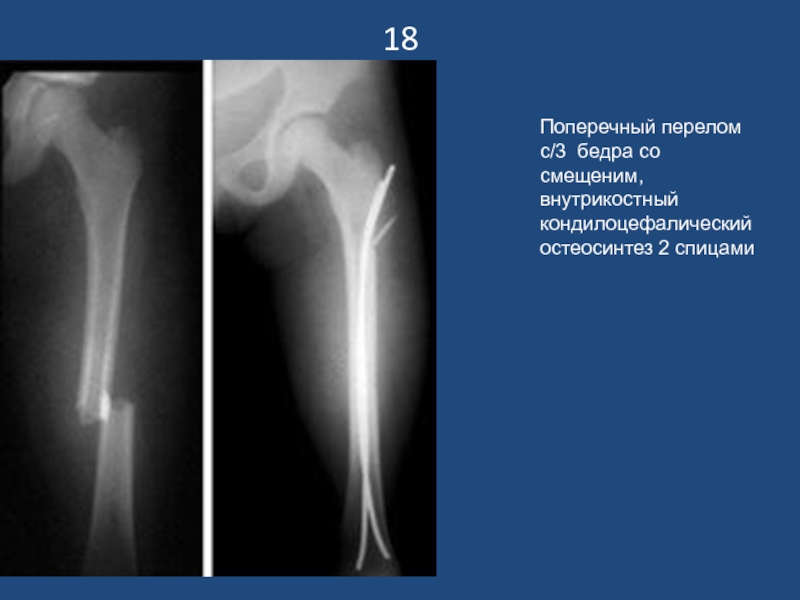

Поперечный перелом с/3 бедра со смещеним, внутрикостный кондилоцефалический остеосинтез 2

спицами

18Поперечный перелом с/3 бедра со смещеним, внутрикостный кондилоцефалический остеосинтез 2 спицами